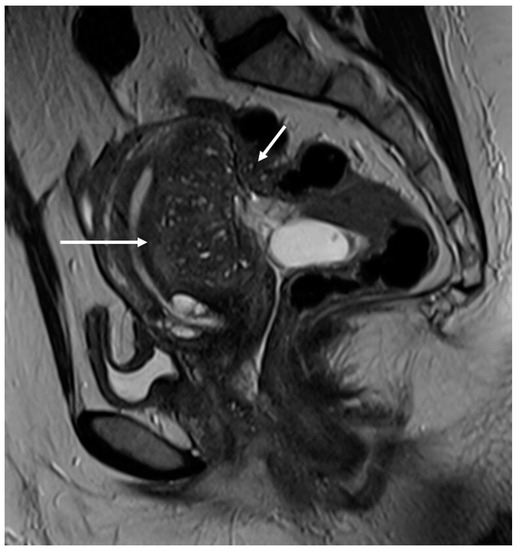

Figure 2.

Deep infiltrating endometriosis of the anterior and posterior compartments in 33-year-old female with dysmenorrhea, chronic pelvic pain, dyspareunia and dyschezia. (A) Sagittal T2WI. Evidence of external anterior adenomyosis and plaque of the vesico-uterine pouch (white arrow); (B) Sagittal T2WI. Retrocervical localization of DIE (white arrow); (C) Axial T2WI. Left uterosacral ligament (USL) localization (white arrowhead), plaque of vesico-uterine pouch (white arrow) with involvement of the round ligaments, particularly on the left (white dotted arrows), and adhesions with the ovaries (retraction of the broad ligaments).

The surgical approach can vary according to the proximal or distal involvement [39].

Involvement of the proximal portion of ligaments (distance less than 2 cm from the cervix) may, in some cases, be associated with thickening at the level of the torus uterinus; in such cases, it is essential to report any mass or thickening in the upper portion of the posterior cervix, as this could cause the surgeon to proceed with a laparoscopic trans-vaginal approach [7] (Figure 2, Figure 3 and Figure 4).

Figure 3.

Right uterosacral ligament localization in a 43-year-old female. The right uterosacral ligament appears thickened at uterine insertion (white arrow).